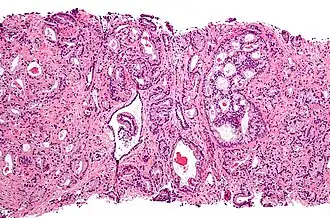

Cancerul de prostată este o formă de cancer care se dezvoltă în prostată, o glandă aflată la intersecția aparatului urinar cu cel genital la bărbați. Mare majoritate a cancerelor de prostată se dezvoltă lent, cu toate acestea, există cazuri în care cancerul de prostată se dezvoltă în mod agresiv.[4] Celulele canceroase se pot extinde prin metastază la oase și ganglioni limfatici. Cancerul de prostată poate provoca durere, disfuncție erectilă, dificultăți de urinare și probleme în timpul actului sexual. Alte simptome se pot dezvolta în timpul unor etape ulterioare ale bolii.